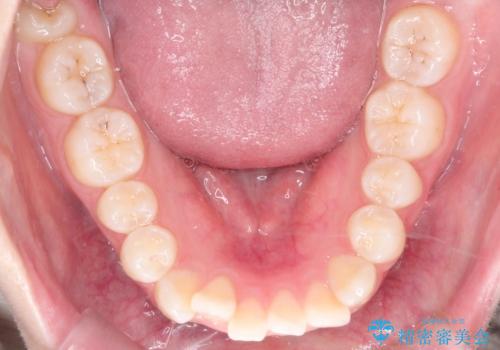

- 前歯のデコボコ(叢生)を気にされてご来院されました。精密な検査の結果、歯が並ぶスペースが不足していることが判明。患者様のご希望から、透明で目立ちにくいインビザライン(マウスピース矯正)による治療計画を立案しました。抜歯を避け、奥歯全体を奥へ動かす遠心移動という方法でスペースを確保し、前歯の叢生を解消することを目指します。

今回の矯正治療では、透明なマウスピース型の装置インビザラインを使用しました。この装置は取り外し可能で、日常生活で目立ちません。治療は、緻密に計算された計画に基づき、段階的に作製されたマウスピースを交換していくことで、奥歯から順に全体を後方へ移動させる遠心移動を実施。これにより、前歯を並べるための十分なスペースが確保され、デコボコが解消されました。抜歯することなく、機能的にも審美的にも整った美しい歯並びを獲得していただけました。